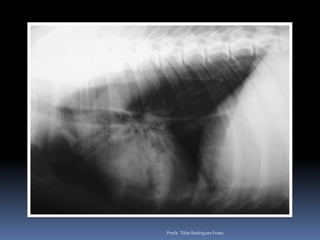

Animal: NEGUER, canino, macho, 11 anosHx: Ascite, sinais de creptação e sopro na ausculta pulmonar - asciteProfa. Tilde Rodrigues Froes

Profa. Tilde Rodrigues Froes

Animal: NEGUER, canino,macho, 11 anosHx: Ascite, sinais de creptação e sopro na ausculta pulmonar - asciteProfa. Tilde Rodrigues Froes

• 24.